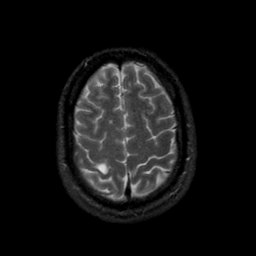

MR Study #9, April 14, 1991 -- Slice #41

[Home][Help][Clinical][Tour 1][Tour 2] Slice 41